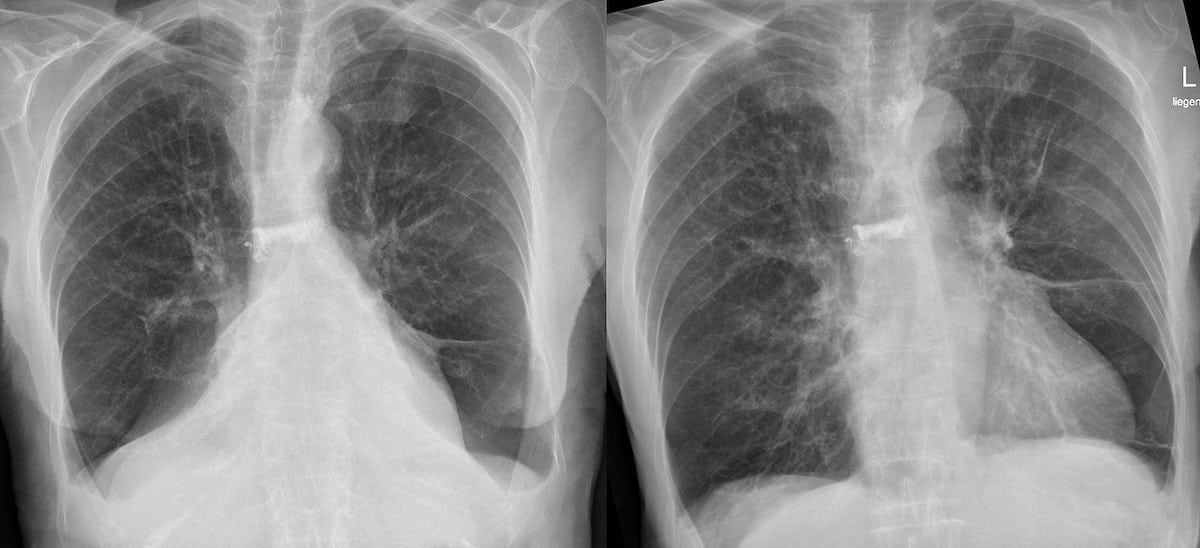

What Does A Healthy Lung Look Like In An X Ray . Also, the diaphragm may look lower and flatter than. However, when it does, doctors may notice visible signs, such as air pockets in lung tissue, a lowered diaphragm, or enlarged. This means the lungs appear larger than normal. Pneumonia in the lungs will most commonly be seen as white areas. Suggest everything is working just. What does pneumonia look like in the lungs? Not quite black, because there is still tissue there, but still quite. There are no visible nodules, tumors or masses. The boundary of the lungs is clearly.